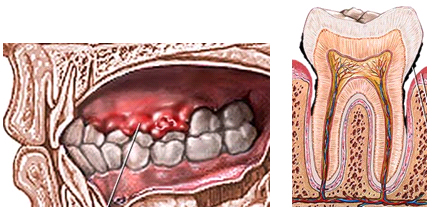

Periodontal Treatments (Gum Treatment) ![]()

Teeth were created with the purpose to last in mouth the entire life of the patient. However, proper care utilizing correct brushing, flossing and mouth rinse is needed daily. With these appropriate actions you will be able to prevent any infections or abnormalities of the gums.

If you have ever seen a TV commercial for tooth paste or tooth brushes, maybe you have hear the word periodontum. The periodontum is the name given to all those structures that surround the tooth and support it in order to maintain proper function in the mouth.

As with most diseases, Periodontitis shows primary symptoms, but if you don’t take action when they appear the disease continues silently and sometimes painless until it becomes a real problem to your health.

The progression of this disease changes from patient to patient. Statistically, it is easy to say that half of the people over 18 years of age have primary periodontal disease symptoms, or as we call it Gingivitis. 3 out of 4 patients over the age of 35 have more advanced stages of periodontal disease.

Remember that periodontal disease is an infection that occurs around the supporting tissues of the teeth, affecting structures like the gum, the periodontal ligament and the bone which provides the ultimate support. It is very easy to loose healthy teeth due to advanced stages of this disease.